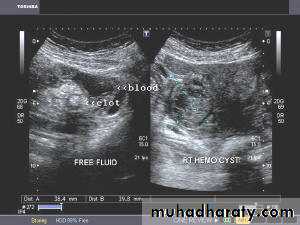

Hemorrhagic cyst of ovary with ruptured ectopic pregnancy:This female patient has a left ovarian hemorrhagic cyst (see ultrasound image above-left). In addition, there is a large collection of free fluid with particulate matter in the pelvis. The right fallopian tube is thickened with a ring shaped mass. This suggests that there is significant hemorrhage into the pelvis due to a ruptured ectopic pregnancy (right tubal ectopic gestation). The left ovarian hemorrhagic cyst appears intact, ruling out ruptured hemorrhagic cyst.